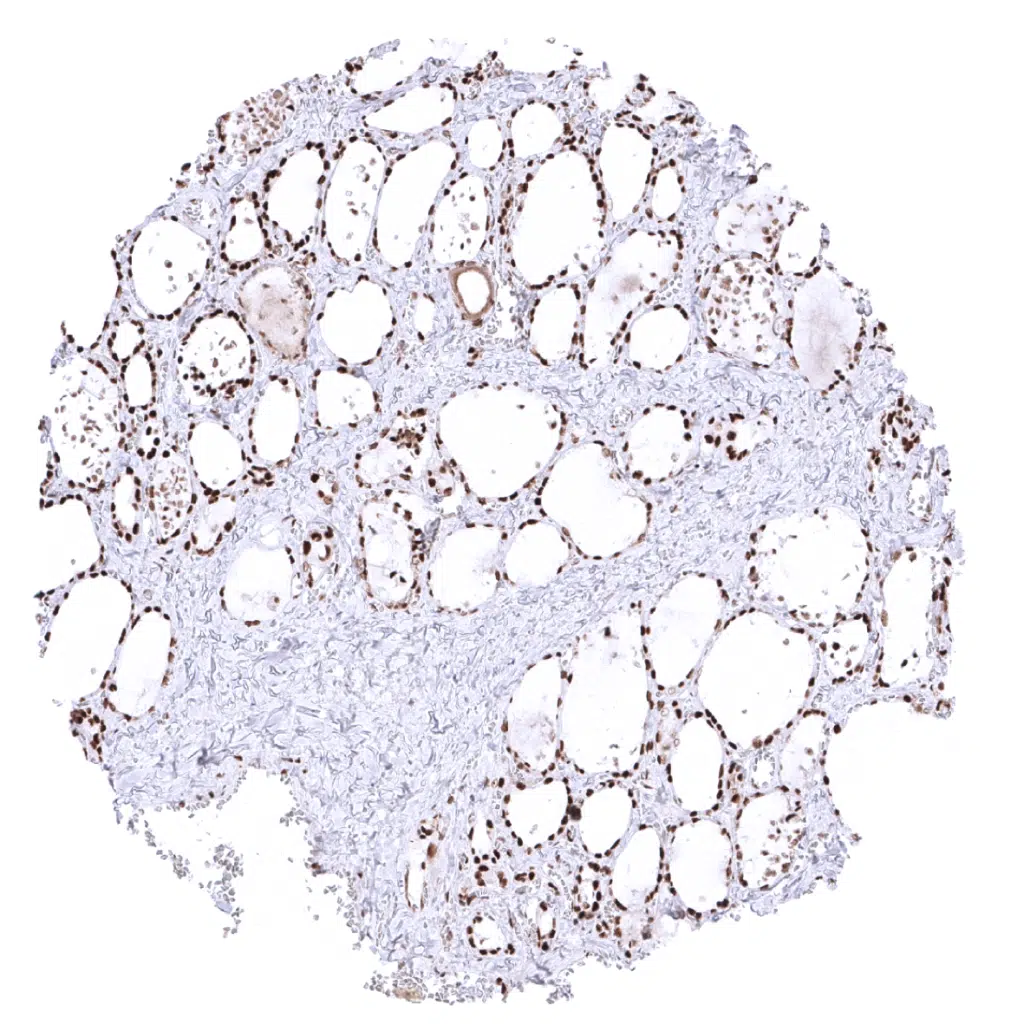

Thyroid gland